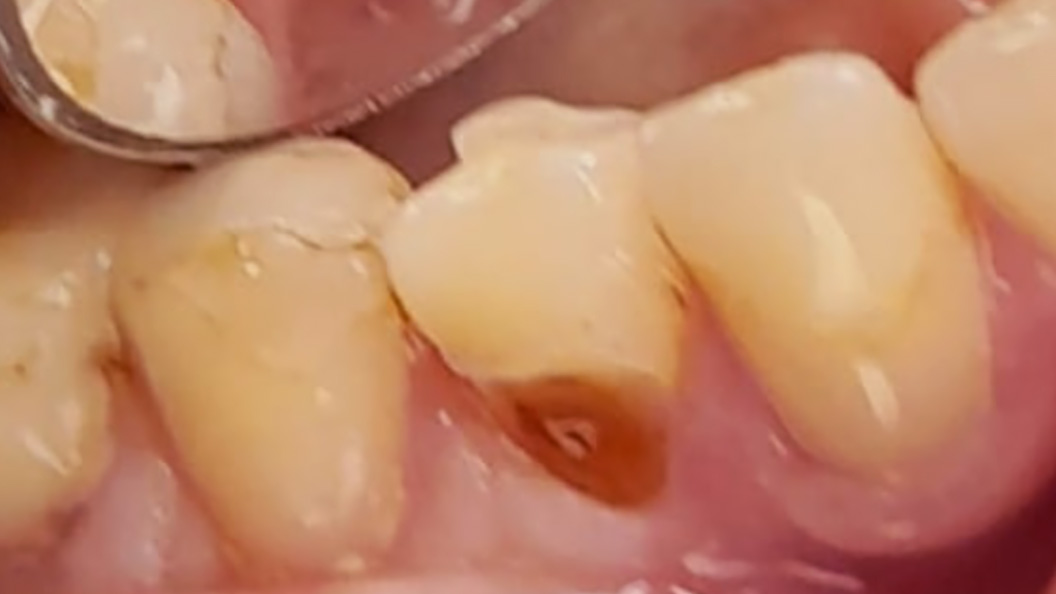

Пациентка обратилась к стоматологу-терапевту с проблемой выпадения пломбы из премоляра нижней челюсти. Её также беспокоила резкая боль в зубе, которая возникает после принятия холодной пищи и напитков, но быстро проходит. Осмотр и диагностика позволили выявить у пациентки наличие глубокого кариеса зуба 44. Ей предложено лечение с установкой светоотверждаемой пломбы.

Глубоким считается кариес на последней стадии развития, когда заболевание поражает не только эмаль, оно уже выходит за пределы дентина. Если на этом этапе не пройти лечение, следующим шагом станет пульпит — воспаление сосудисто-нервного пучка зуба. Для профилактики заболеваний полости рта необходимо соблюдать ежедневную гигиену и проходить профилактический осмотр у стоматолога не реже двух раз в год.